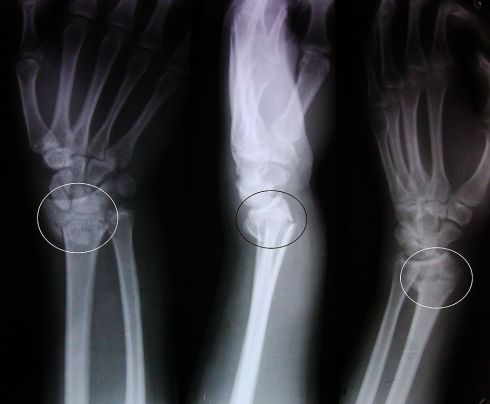

After waiting six hours at Medway we were seen at 3am by an orthopedic specialist who announced he would have to straighten Clarissa’s strangely bent arm, it was, said the tired doctor, “a dinner fork fracture”, a literal description of the shape of her arm, which had been forced into her wrist. Straighten it now he meant as he called for help, no anesthetic just two men pulling and tugging at her wrist and elbow.

Straightened to his satisfaction her arm was fully plastered, “What colour would you like?” said the smiling plasterer. “White” we said in unison, because we’re traditionalists. He shook his head sadly, “We’ve red, blue, and pink.” Pink turned out to be a shade I’d call ‘kinky pink’ so we went for that. Another wait in a bleak corridor for an x-ray, you can just see the pink plaster in the reflection, then home as dawn broke.

A few days later and we’re back in Chatham seeing the consultant. “It’s a positive Terry Thomas.” He almost beamed, a little too pleased with himself, “we’re probably going to have to operate.”

We asked to be transferred to Lewisham hospital, and so a week later we’re seeing a different consultant. This one looked a bit like Boris Johnson but without the bedside manner. By way of a hello he said ‘”I hope you realise how serious this is?” His students milled around the x-ray, clucking. “We’ll have to wait for it to mend, then break it again and insert a plate.”